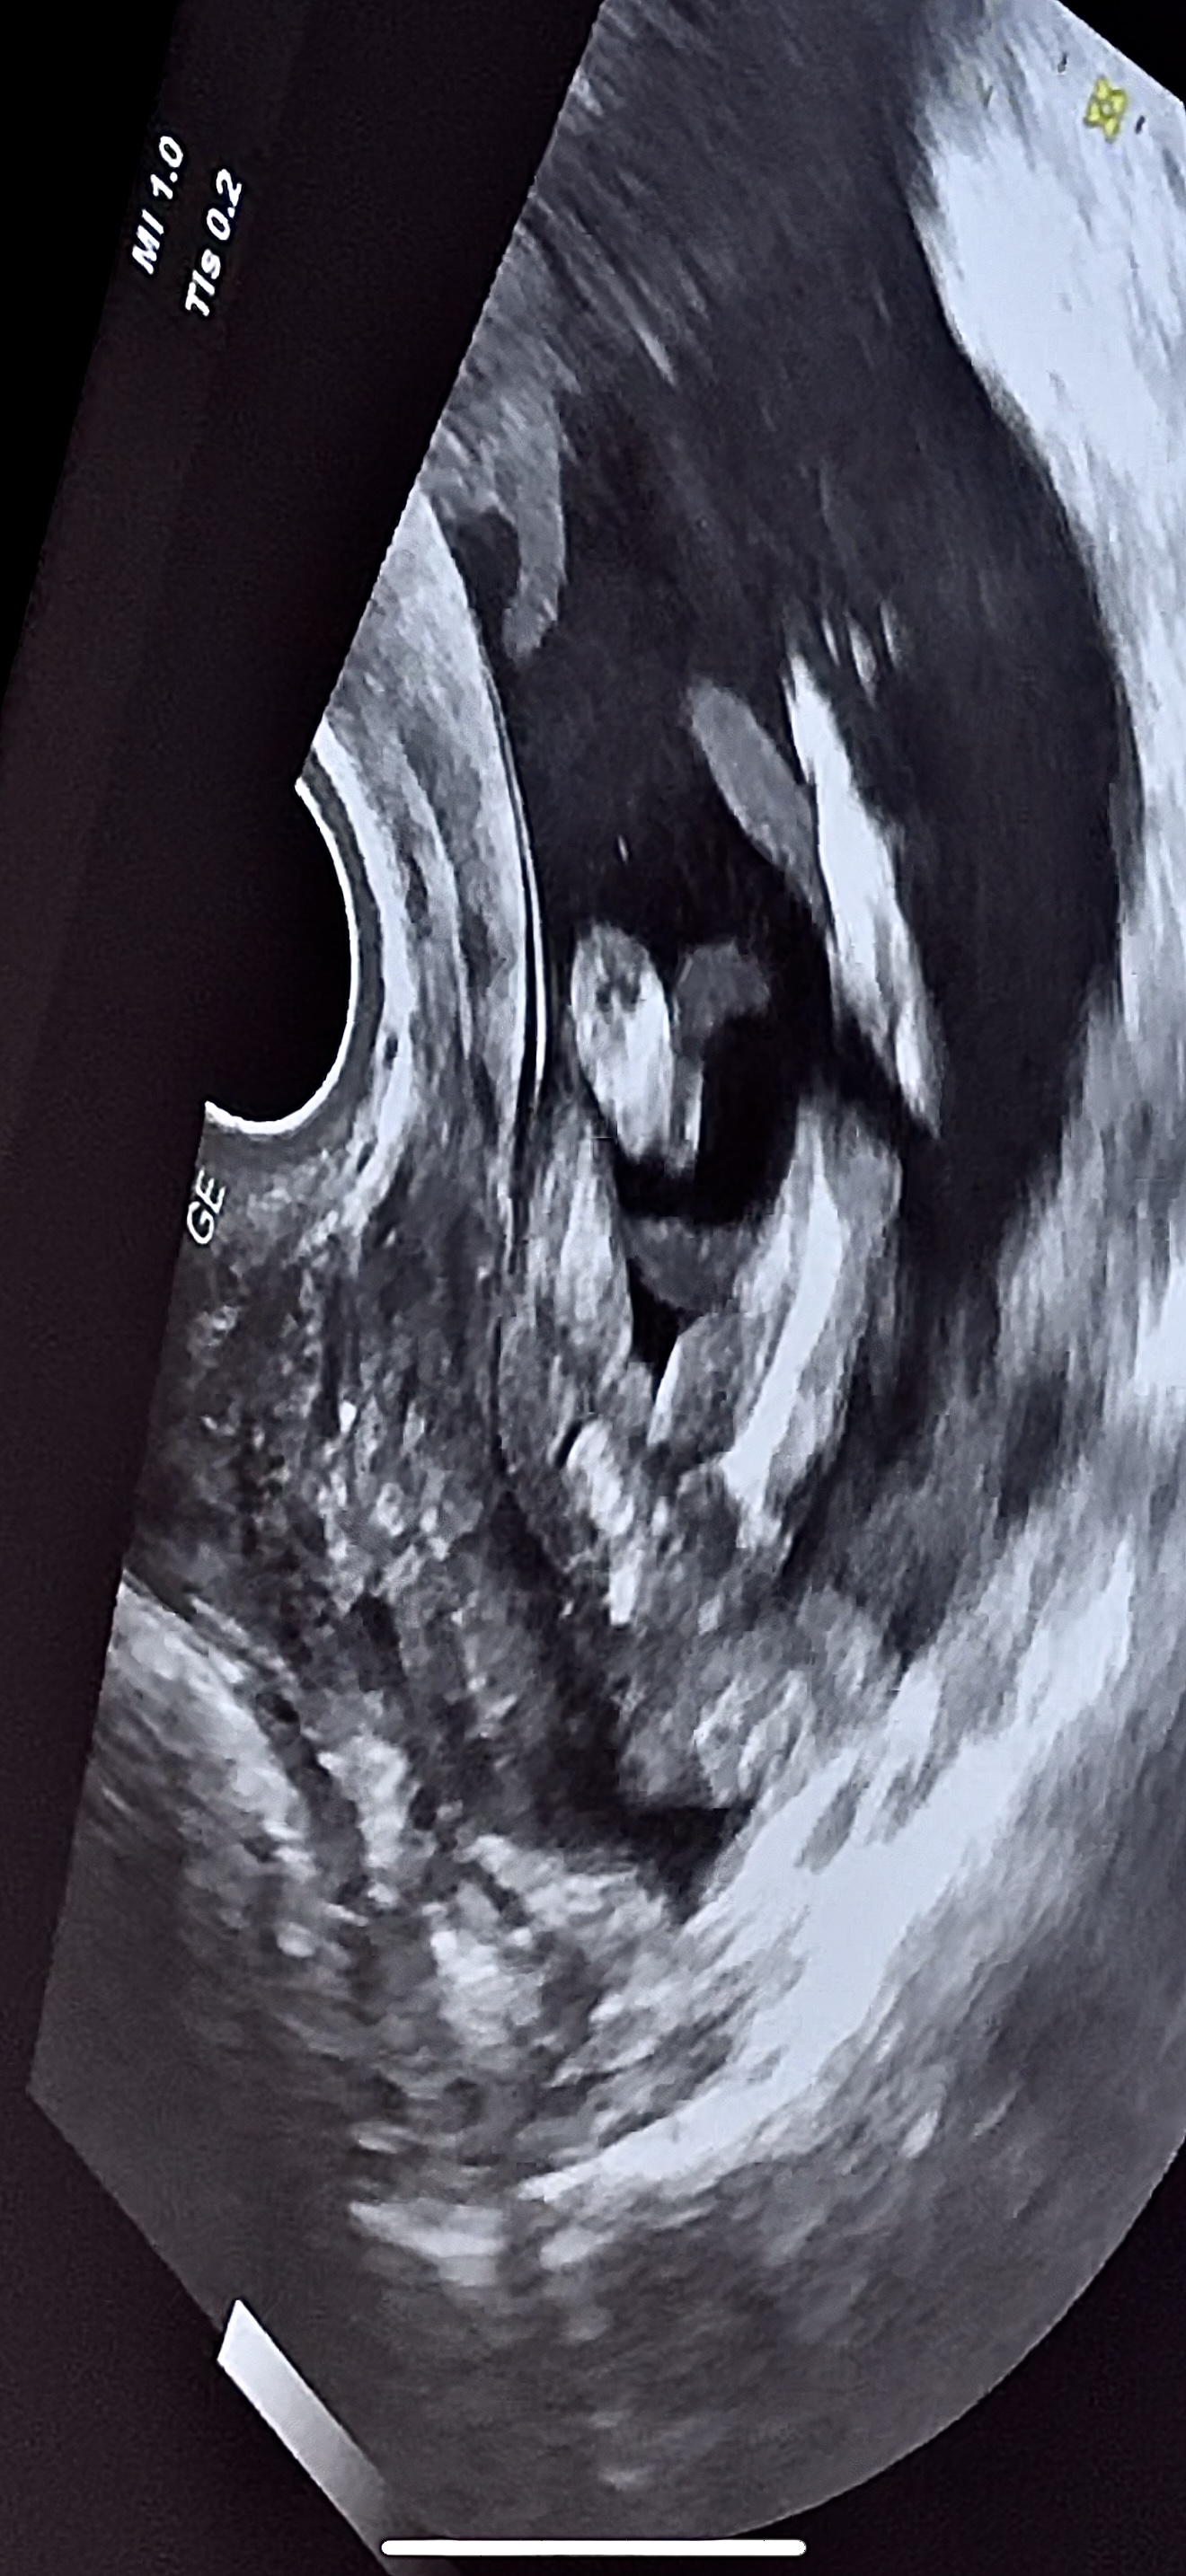

Кто в теме, подскажите пжста, веду беременность платно, на первом скрининге за пол я не спрашивала, так как понимала что срок маленький совсем. На 11 неделе делали. Далее перед отпуском решила сходить сделать узи платно, подсмотреть так сказать за малышом)) Было 14 - почти 15 недель. Я шла просто подсмотреть! А узист закончив первые важные замеры, спросила а не говорили ли мне уже пол? Я ответила что нет, маленький ведь срок. На что она мне сказала ну тут уже все очень даже видно, мальчик у вас будет! Заявила на все 100% и все оставшееся время пока мы там все рассматривали , ручки ножки, она раз 10 сказала что пистолетик видно 😂 Прям уверила . Но мне, честно, тоже показалось сразу это самое, как только началось узи. Фото приложу. И вот вернулась я с отпуск, думаю схожу еще раз , а то второй скрининг только 12 марта. И что вы думаете? В этот раз она молчала на счет пистолетика про который твердила в первый раз 🙈🫠 17 недель и 3 дня по последний мес 🩸 и по малышу написала 16 недель 9 дней. Как в аптеке 😅 Сказала что-то сегодня не видно ничего. Короче малость я расстроилась конечно.. когда тебя так сильно уверяли, а сегодня вот такое) Еще и фотку распечатала пистолетика, сказала мужу показать) эхх Все фото это 14-15 недель